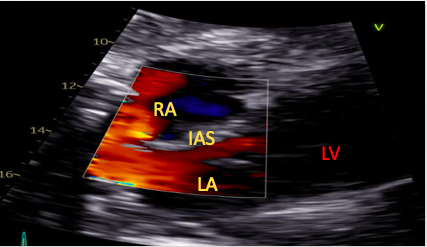

The standard SC four-chamber view provides clear visualization of both atria allowing for assessment of numerous pathologies including myxomas, masses, and atrial thrombi.19,20 The interatrial septum can also be visualized in this view and runs almost perpendicular to the ultrasound beam, allowing for a thorough assessment of septal pathology using both color flow Doppler interrogation and contrast echocardiography (Figure 2).21

Figure 2. Subcostal view with color assessing the interatrial septum for the presence of abnormal flow.

RA=right atrium, LA=left atrium, LV=left ventricle